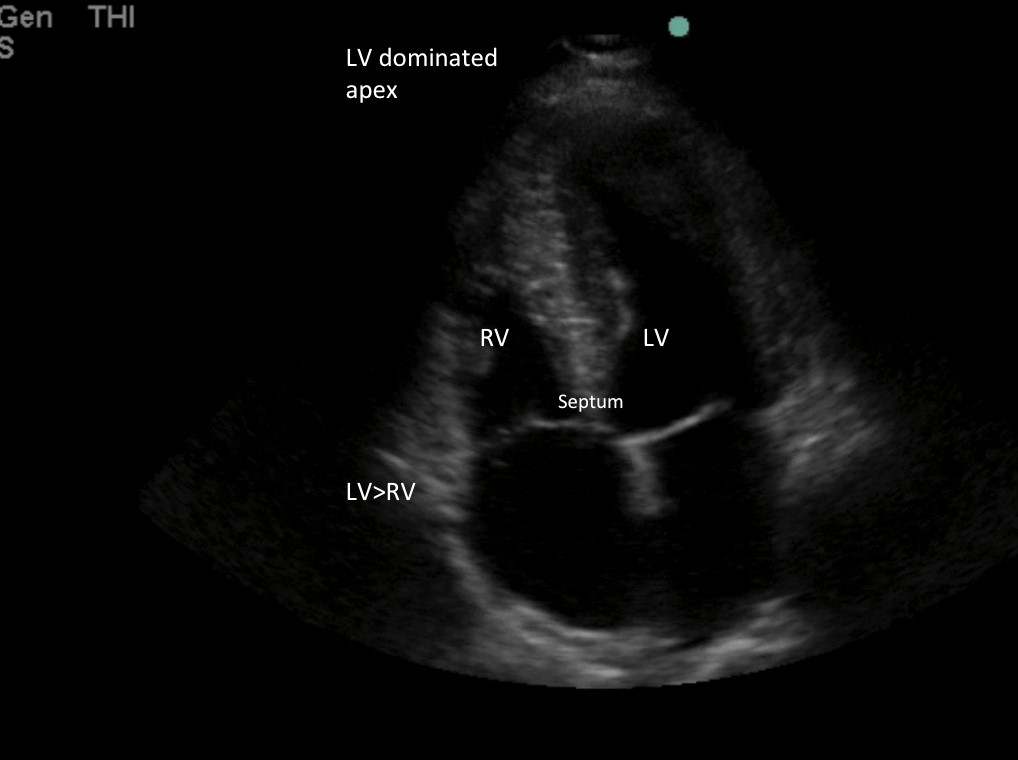

画像3:正常なRVサイズはLVサイズの⅔以下で、頂部はLVに支配されている